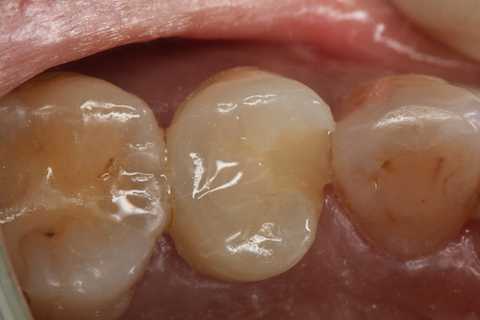

40代女性、左上5、冷水痛+

今回この方は5本のCR充填を一挙に行ったので、かなり疲れた。

では時系列でどうぞ